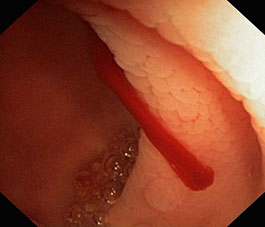

Sonda de Alimentación Nasoyeyunal Colocada por Endoscopia

Una sonda de alimentación es un dispositivo médico que se utiliza para proporcionar nutrición a pacientes que no pueden alimentarse por vía oral, son incapaces de tragar con seguridad o que necesitan suplementos nutricionales. La sonda nasoyeyunal (NJ, por sus siglas en inglés) es un tubo que lleva los alimentos a través de la nariz hasta el yeyuno (parte del intestino delgado). La sonda NJ es suave y flexible para que pueda pasar fácilmente a través de la nariz y el estómago. Esta indicada cuando se pronóstica que el paciente necesitará alimentación asistida por mas de 1 mes hasta valorar su recuperación.